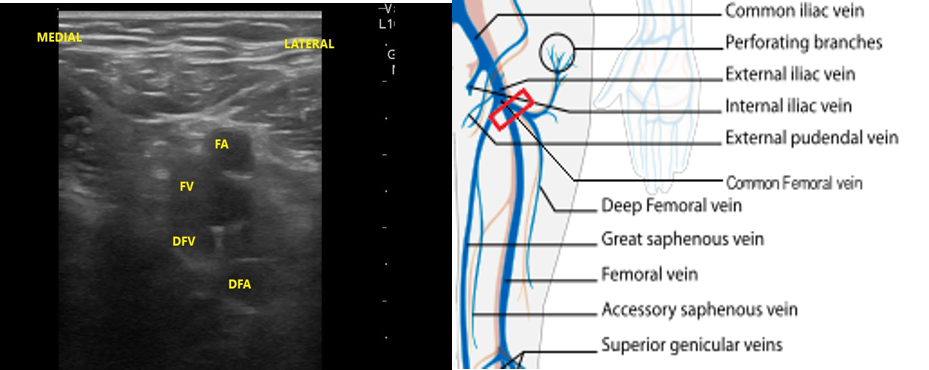

- The first venous confluence is the great saphenous vein (GSV) and common femoral vein (CFV). The GSV joins the CFV medially.

- The CFV forms a few centimeters distally to the GSV confluence, formed by the deep femoral vein (DFV) and femoral vein (FV). (The femoral vein is occasionally referred to as the superficial femoral vein, but as this structure is actually considered part of the deep venous circulation, it will be referred to as the femoral vein for the rest of this discussion.)

- The common femoral artery (CFA) splits at the same location (generally just proximal to the formation of the CFV) and forms the deep femoral artery and femoral artery (FA). From this point, the deep arteries and veins disappear from view, but the FA and FV can be imaged along the medial thigh until the adductor canal (AC), just proximal to the medial knee. The FA will be seen as the more superficial pulsatile structure with the FV just deep to the FA.

- Slide the transducer distally 1 to 2 cm to the junction of the CFV and GSV ( 10 and 11) and compress.

- Figure 10. Junction of the CFV and GSV 1-2 cm below the inguinal canal with transducer orientation indicated (red rectangle).

- Figure 11. Compression of the CFV at the junction of the GSV 1-2 cm below the inguinal crease.

- Slide the transducer another 1 to 2 cm (3-4 cm distal to the inguinal ligament) to the junction of the DFV and FV. You will also see the CFA branch into the FA and DFA (Fig. 12). This constitutes completion of evaluation of “region 1.”

- Figure 12. Visualization of the DFV and FV just distal from where they converge into CF with transducer orientation indicated (red rectangle).